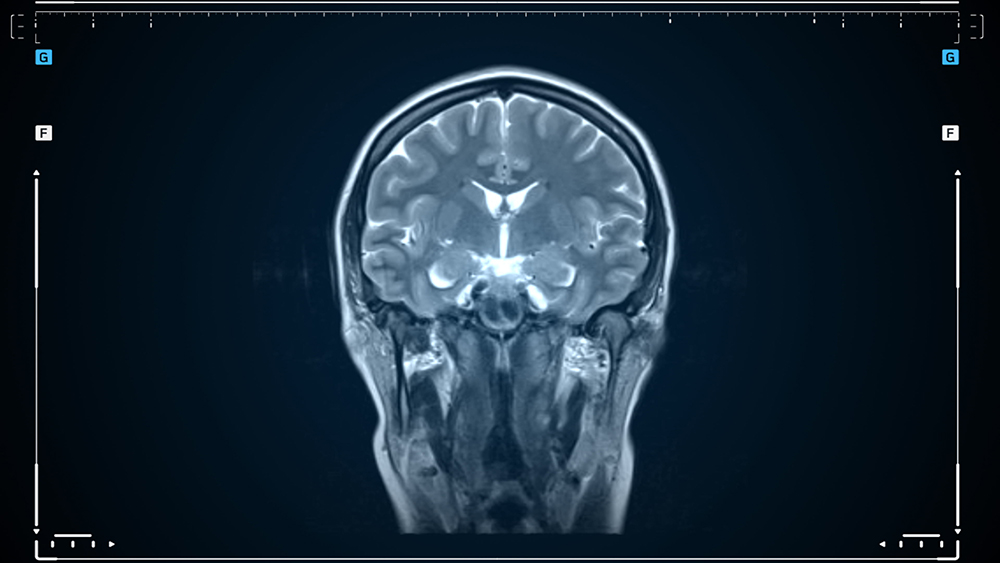

- MRI 및 MRA: 뇌혈관의 구조와 혈류를 확인하기 위한 주요 영상 진단 방법입니다.

- 뇌혈관 조영술: 모야모야병의 확진을 위해 가장 효과적인 검사로, 뇌혈관의 비정상적인 모양을 정확히 확인할 수 있습니다.

- SPECT 검사: 뇌혈류 상태를 확인하며, 병의 진행 정도를 파악할 수 있습니다.